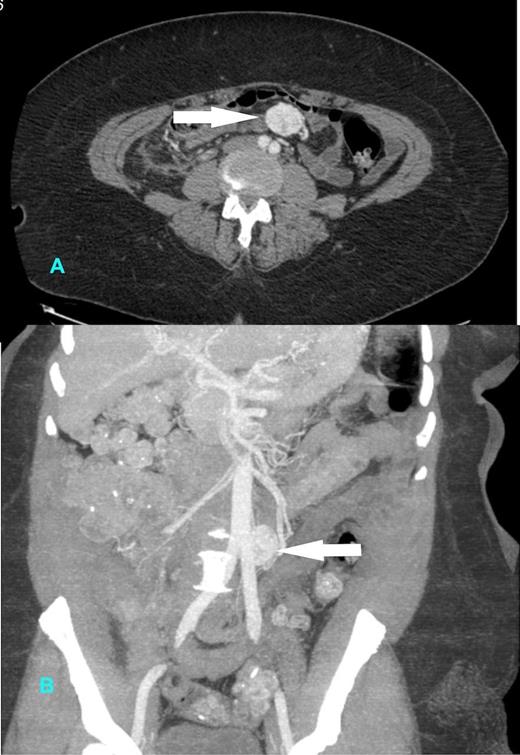

A 64 year old lady was admitted with a short history of abdominal pain. Her past medical history included an ERCP for choledocholithiasis and hypertension. CT scanning revealed a 3.3cm mass within the small bowel mesentery and a shrunken gallbladder. (Figure 1 a, b). The mass enhanced avidly and heterogeneously, with arterial supply from the superior mesenteric artery.

CT Scan showing 3.3 cm avidly enhancing mass (arrow) in the small bowel mesentery with arterial supply from the superior mesenteric artery (A) horizontal and (B) coronal section